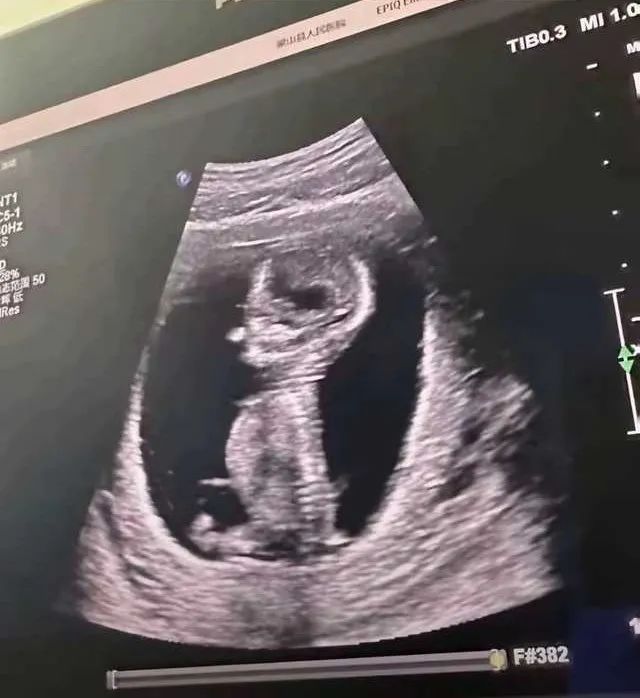

做个 B 超这么